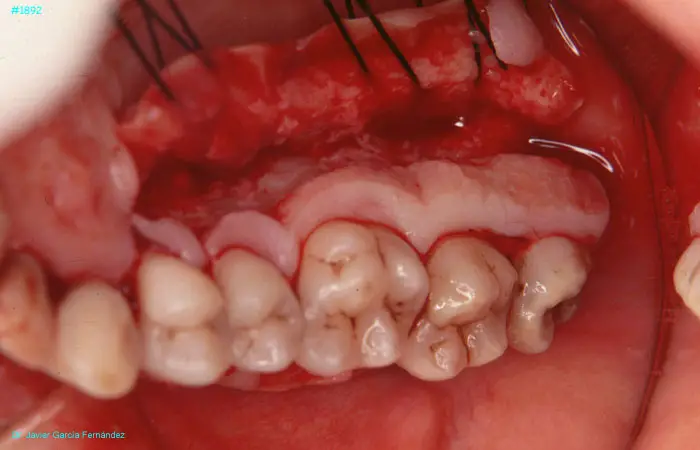

image 38